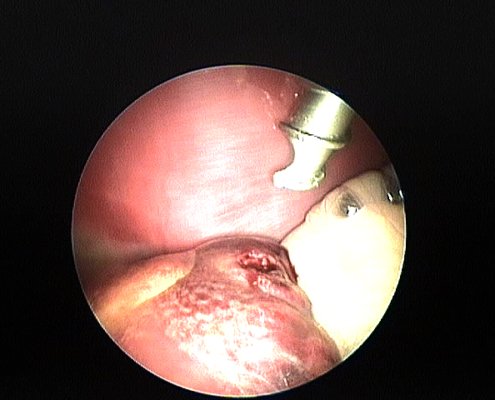

La videoendoscopia, colonoscopia, gastroscopia, rinoscopia… evitan gran número de cirugías abiertas, solucionando problemas como ingestión de cuerpos extraños, posibilita diagnósticos tanto digestivos como respiratorios. Por otro lado, la videoendoscopia sumada al láser azul permite realizar cirugías mínimamente invasivas